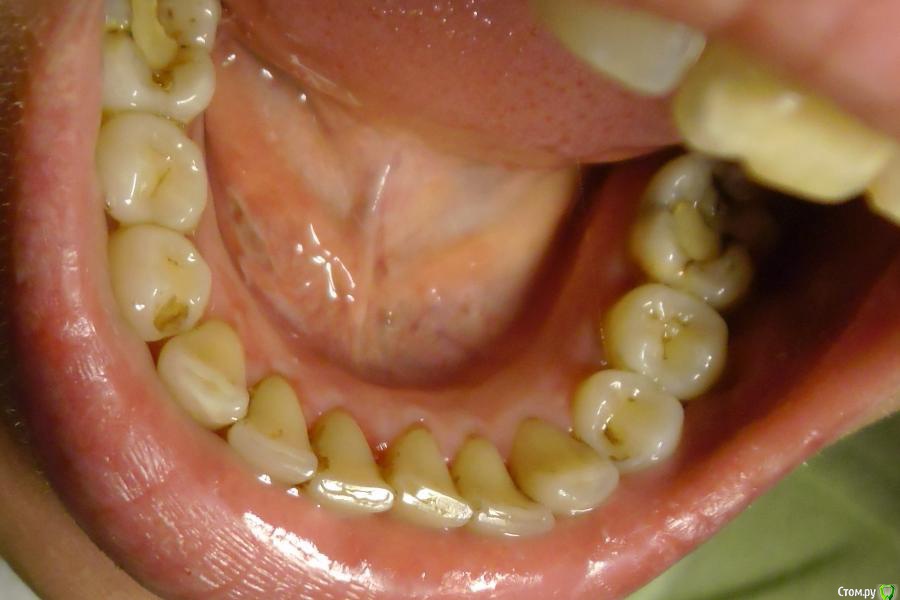

LAnna Опубликовано 17 сентября, 2015 Поделиться Опубликовано 17 сентября, 2015 (изменено) День добрый!Очень прошу помочь мне и оценить качество работы терапевта. 2 дня назад сделала профессиональную чистку в стоматологии (Air Flow) и результат очень расстроил. Но, я не специалист. Может Вы что скажите?И ещё есть несколько, на мой взгляд, моментов, которых быть не должно.1. Врач «просверлил» мне 2 дырки в нижнем нёбе, под языком, которые очень сильно болели. Язвы видно на фото.2. Врач в процессе чистки направлял струю аппарат по направлению к горлу и после процедуры осталось ощущение, как при простуде, когда начинает болеть горло.3. После процедуры воспалился лимфоузел под челюстью с левой стороны. Снизу челюсть опухла.4. Температуру я не мерила, но, по своему состоянию, я могу предположить, что она поднялась.Есть ещё несколько моментов, которые лично мне не понравились, хотя может это и нормально при такой процедуре. Врач работал один, без медсестры. В рот положили слюноотсос. А всё, что вылетало из аппарата, разлеталось в нос, лицо и просто вокруг. Хорошо, хоть мне одели очки (которые буквально через пару минут были залиты разлетающимися брызгами), шапочку, маленький слюнявчик и пару салфеток сверху слюнявчика. В результате, когда я встала после процедуры, все руки и часть моей одежды были в брызгах крови. Доктор выглядел не лучше – как в фильмах ужасов, вся в кровавых брызгах. И вся аппаратура, стол, кресло выглядело так же. Зрелище ещё то… После процедуры доктор не озвучил никаких рекомендаций – чего нежелательно есть какое-то время, чем облегчить состояние кровоточивых дёсен и двух «пробуренных» дырок.Плюс ко всему, на мой взгляд, качество чистки оставляет желать лучшего. Я обратилась за процедурой чистки, чтобы удалить налёт (раньше курила - налёт остался), а после пройти лечение. Но, на мой взгляд, налёт во многих местах остался.Пожалуйста, скажите своё мнение, как профессионалы, по этой ситуации.Спасибо.P.S.Прошу простить за качество фото. Изменено 17 сентября, 2015 пользователем LAnna Ссылка на комментарий

Scrabble Опубликовано 17 сентября, 2015 Поделиться Опубликовано 17 сентября, 2015 (изменено) Чтобы было чисто- чисто, надо ещё ультразвуком почистить. Эйрфло- процедура довольно инвазивная для слизистых оболочек, поэтому при чистке должны соблюдаться некоторые правила: работа в четыре руки, использование пылесоса, расположение наконечника под определённым углом. Лимфоузлы воспалились в ответ на повреждение слизистой- это пройдёт. Рекомендации, конечно, желательны( ротовые ванночки с 0,05% р-ром хлоргексидина после каждой еды в течение пары дней, солкосерил дентальный адгезивный гель на повреждённые участки после полоскания хлоргексидином).До заживления исключите всё острое, солёное, очень горячее. Когда всё заживёт, лечите кариесы. Изменено 17 сентября, 2015 пользователем Scrabble 2 Ссылка на комментарий

LAnna Опубликовано 18 сентября, 2015 Автор Поделиться Опубликовано 18 сентября, 2015 Продолжение истории.Сегодня была на приёме у этого доктора - озвучила ей своё недовольство полученным результатом (качеством и неприятными последствиями). На это она ответила, что в моём случае УЗ чистка не подойдёт, т.к. она только для удаления камней. Чёрный налёт, который остался у меня на нижних передних зубах она в упор не видит, а коричневый пятна - это "пигментные пятна, которые чисткой не удаляются". А мои жалобы на воспаление лимфоузлов и двух дырок под языком вообще пропустила мимо ушей. Кстати, некоторые пятна крови, которые появились на оборудовании во время моей процедуры профессиональной чистки до сих пор красуются в кабинете доктора. Вот такая история.Для себя я решила, что займусь активным поиском хорошего специалиста, который сможет реально мне помочь в данной ситуации.Никогда не думала, что у меня всё так запущено, что мне уже ничего не поможет... Ссылка на комментарий